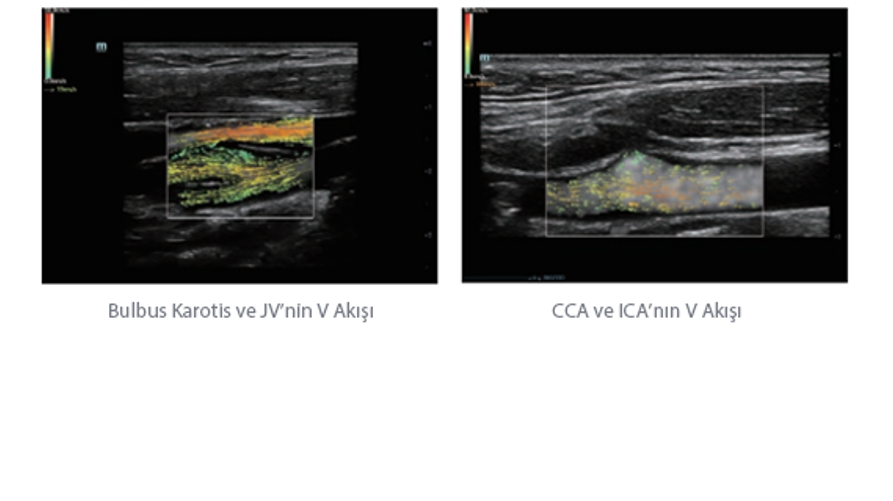

Resona 7, ĂŒstĂŒn dĂŒzeyde g?rĂŒntĂŒ kalitesine ek olarak, vaskĂŒler hemodinamik de?erlendirmesi i?in devrim niteli?indeki V Ak??? ile fetĂŒs CNS tan?lamas? i?in 3 boyutlu veri kĂŒmesinden dĂŒzlem g?rĂŒntĂŒsĂŒ alma konusunda en iyi birime sahip oldu?undan, klinik ara?t?rma yeterliklerini de art?rmaktad?r. En sezgisel, harekete dayal? ?oklu dokunmatik i?letim ile tĂŒm temel klinik ?zellikleri bir araya getiren Resona 7, ultrason yenili?i konusunda ger?ek anlamda yeni dalgalara ?ncĂŒlĂŒk ediyor.